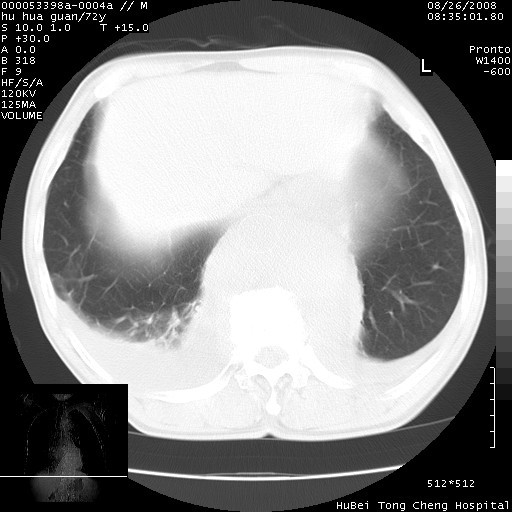

标题: CT15582:M,72Y。请老师帮分析胸部病变。

考虑胸主动脉下段夹层破裂。

考慮夾層動脈瘤破裂可能,建議增強掃描。

可以明确的说。肯定不是主动脉夹层破裂出血!考虑为淋巴瘤或间叶组织来源的恶性肿瘤可能性大。右肺小结节建议薄层观察,如能发现恶性征象,那椎前改变就考虑为转移所致。至于双侧少量胸水乃静脉血回流受阻所致。

图像及窗宽窗位均不理想。周围性肺癌/胸腔积液/纵隔积液。

1、右肺周围性肺癌、胸腔积液(双)

2、建议食道吞钡和增强检查排除食道和主动脉病变

3、后纵隔淋巴类肿瘤

1、右上肺结节病变,肺泡癌不除外,请随诊;左下肺近后纵隔病变,考虑纵隔型肺癌侵犯大血管可能;

2、右下肺背段少许炎症,双侧胸腔积液,右下肺纤维索条。

降主动脉前移位,后纵隔占位

后纵隔占位,降主动脉前移位;双侧胸腔积液;应排外食管病变侵犯血管可能;

主动脉瘤破裂

建议排除结核引起的冷脓肿。